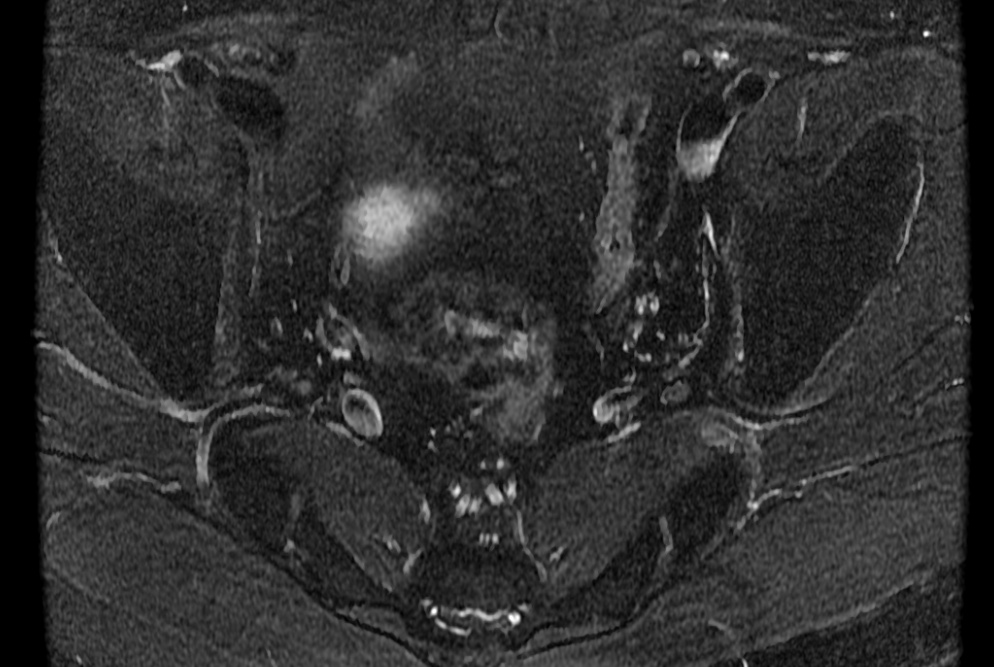

Bilateral sciatica

Bilateral accessory piriformis muscles at the S2 level attaching to the sacral body, anterior the S2 nerve roots. Normal piriformis muscles should be posterior to the sacral nerve roots. The result is that the S2 nerve roots may be pinched between the piriformis and accessory piriformis muscles.

Bilateral accessory piriformis muscles